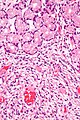

Inflammatory fibroid polyp. H&E stain.

LM proliferating spindle cells - loosely arranged round blood vessels with perivascular hypocellular zones, eosinophils (usually prominent), +/-leiomyoma/schwannoma-like areas - with nuclear palisading

• Proliferating spindle cells (fibroid) - key feature.

• Loosely arranged, concentrically, around blood vessels.[3]

• Perivascular hypocellular zones.[1]

• Inflammation:

• Eosinophils - often prominent.

• +/-Leiomyoma/schwannoma-like areas - with nuclear palisading.[1]